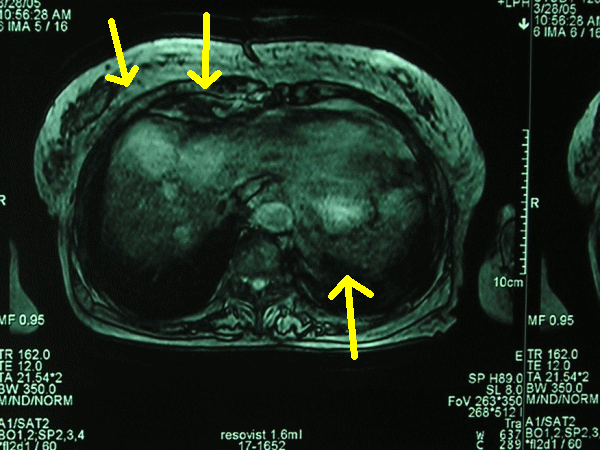

MRI @ƒŠƒ]ƒrƒXƒg‘’‰eB4`5‚ƒ‚‘ε‚ΜŽξᇂͺ

3ŒΒ‚ ‚ιB